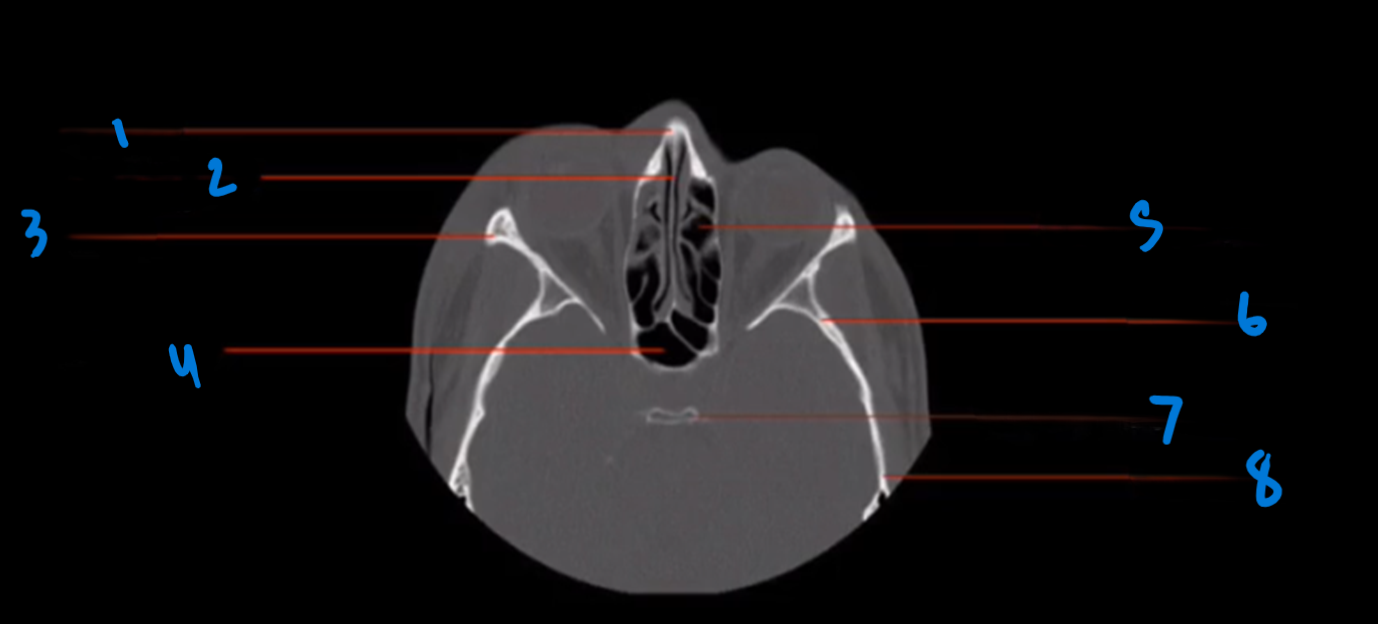

What is the landmark of # 1 called?

Frontal Bone

What is the landmark # 2 called?

Frontal Sinus

What is landmark # 3 called?

Orbital roof

What is landmark # 4 called?

Sphenoid Sinus

What is landmark # 5 called?

Ethmoid air cells (sinus)

What is landmark # 6 called?

Sphenoid bone

What is landmark # 7 called?

Dorsum Sellae, sphenoid bone

What is landmark # 8 called?

Temporal Bone